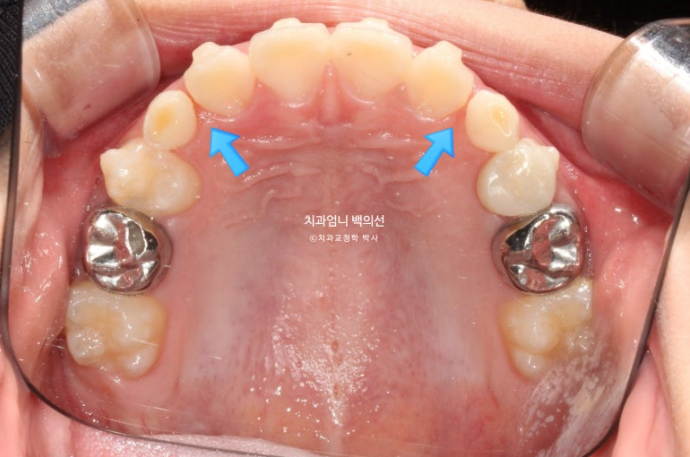

측절치와 송곳니날 자리가 부족해서 악궁확장도 필요한 상황입니다.

악궁확장으로 파란 화살표 반대교합이 해소가 되면서 교합간섭이 사라졌습니다.

악궁확장으로 넓어진 악궁 덕분에 공간이 좁아 못 나오던 측절치도 잘 나오고 있습니다.

아래턱의 위치는 잘 유지되고 있으며 이제 측절치가 충분히 나와 재제작에 들어갑니다.

측절치를 포함한 앞니는 잘 배열 되었습니다.

유치송곳니 벌어진 부분은 영구치 송곳니가 나올 때 공간이 부족하지 않도록 의도적으로 형성한 공간입니다.

영구치 맹출 공간은 충분하고 배열과 중심선 교합 모든 게 좋습니다.